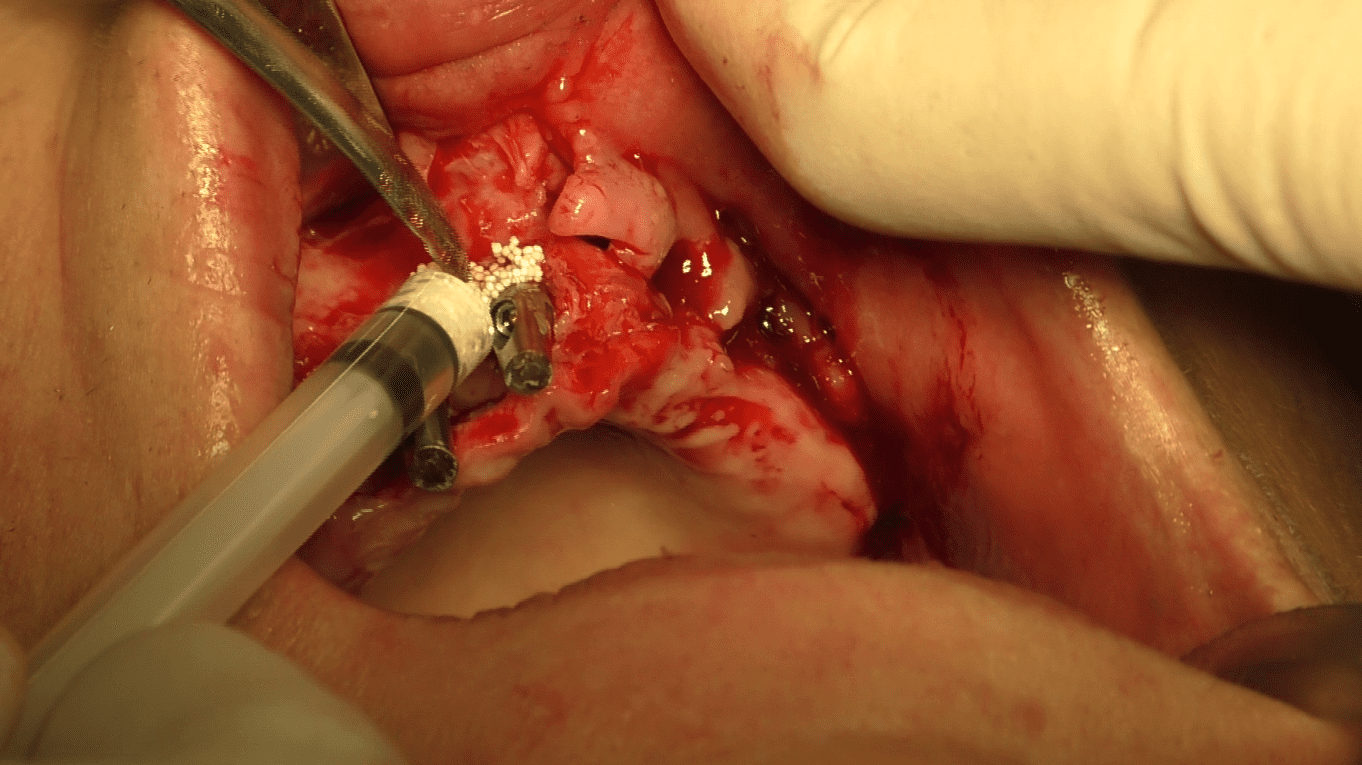

Interventi Preventivi per l’Eccellenza Estetica:

Prima dell’intervento implantare, affrontiamo le atrofie e le zone problematiche attraverso interventi preventivi. Il nostro obiettivo è ottenere non solo una funzione masticatoria ottimale ma anche una soluzione estetica preventivata con il paziente. Garantiamo circolari fissi in ceramica senza falsa gengiva, con elementi dentali che emergono naturalmente senza aggiunte antiestetiche.

Una Serie di Piccoli Interventi per un Grande Risultato:

La chiave del nostro successo estetico funzionale è la realizzazione di molteplici piccoli interventi di correzione e mantenimento dei volumi. Ogni dettaglio contribuisce al risultato finale, garantendo un sorriso naturale e duraturo.